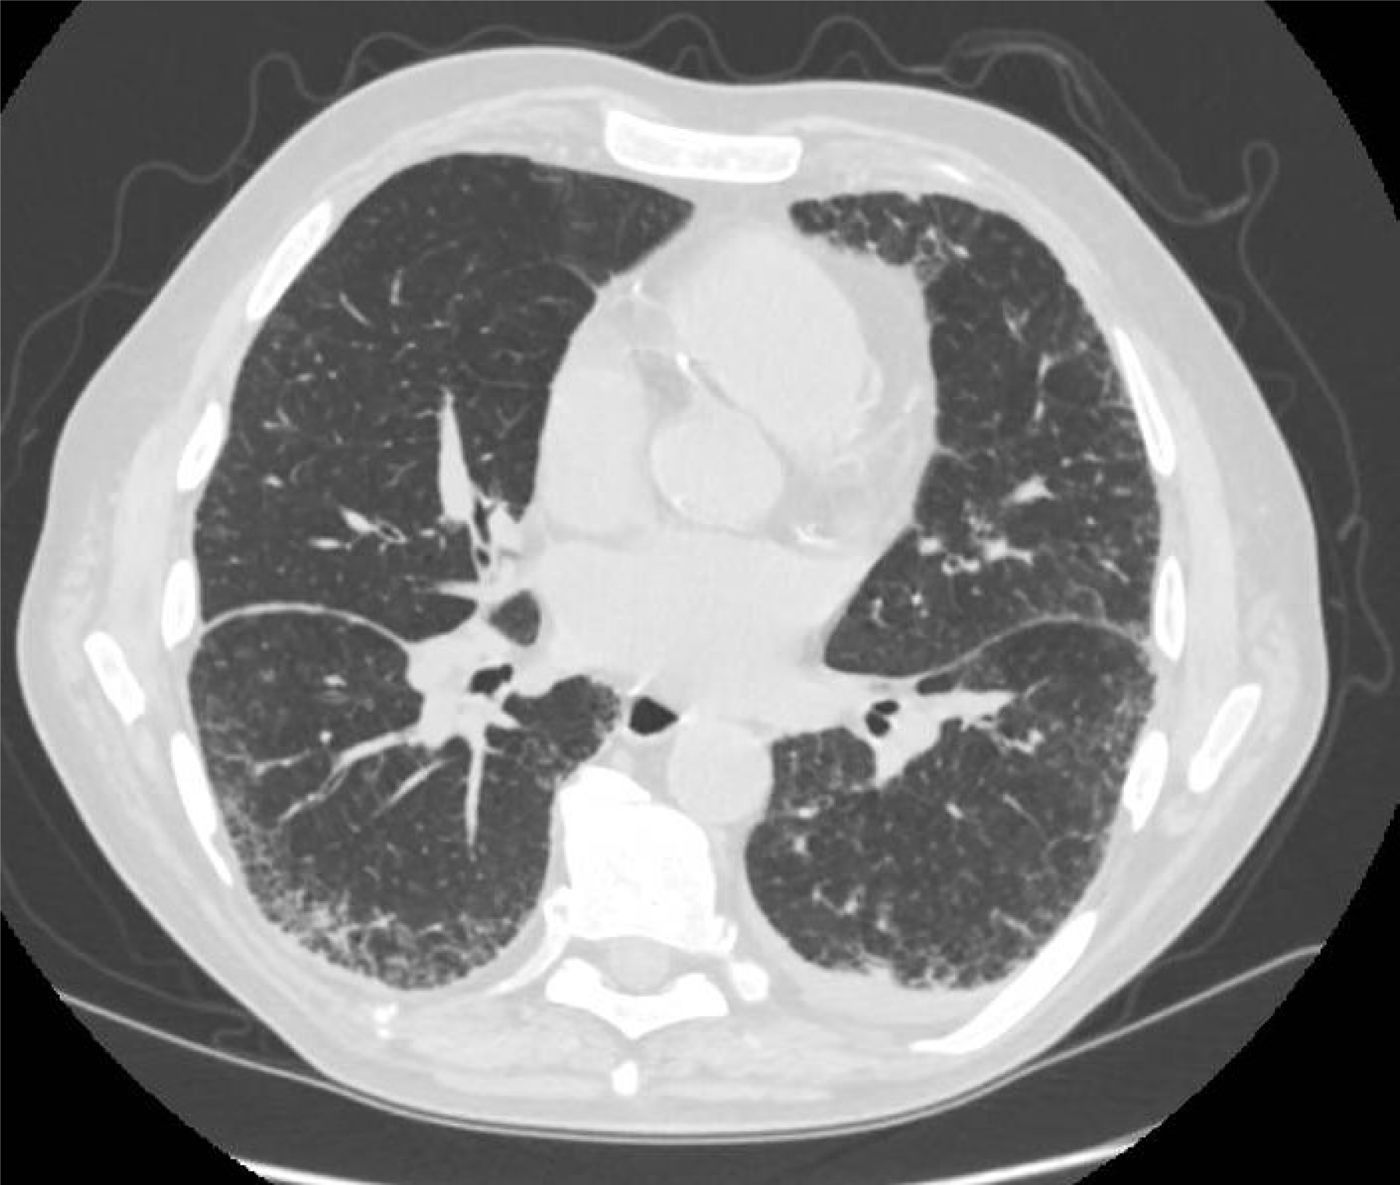

A 66-year-old man, former smoker, with a history of rheumatoid arthritis (RA), low-risk myelodysplastic syndrome (MDS), and chronic kidney disease, was followed in pulmonology for suspected interstitial lung disease (ILD). High-resolution computed tomography (HRCT) (Fig. 1) showed peripheral and bilateral interstitial reticulation with traction bronchiectasis and basal predominance, without honeycombing, consistent with a probable usual interstitial pneumonia (UIP) pattern. These findings showed progression compared with the previous CT scan, with increased extent of reticulation and traction bronchiectasis, without development of honeycombing.

In our patient, the HRCT pattern of probable UIP may be compatible with RA-associated ILD. However, the presence of progressive cytopenias, macrocytic anemia, and the subsequent identification of a somatic UBA1 mutation supported the diagnosis of VEXAS syndrome as the underlying systemic disorder, highlighting the potential overlap between RA-associated lung disease and VEXAS-related inflammatory manifestations.